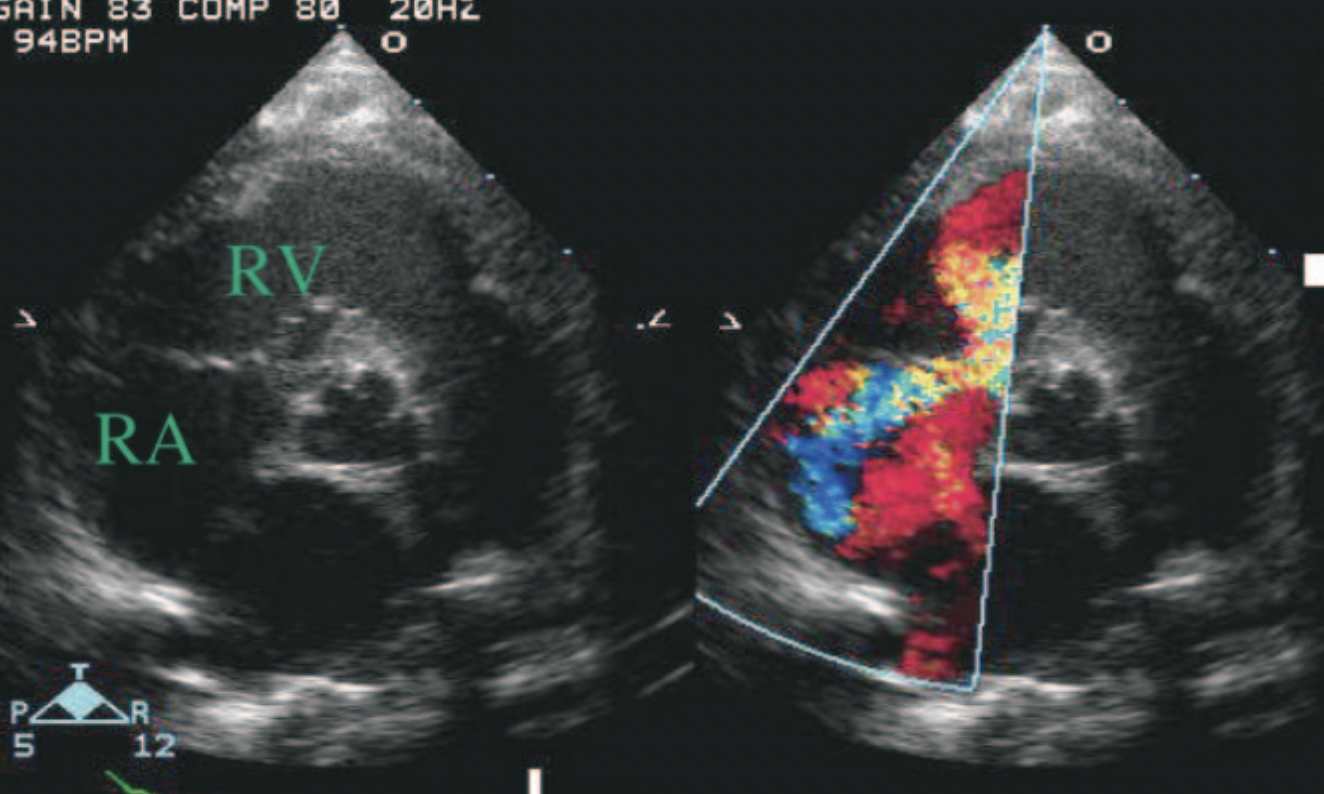

22

Q

What specific kind of VSD is this?

A

Gerbode Defect